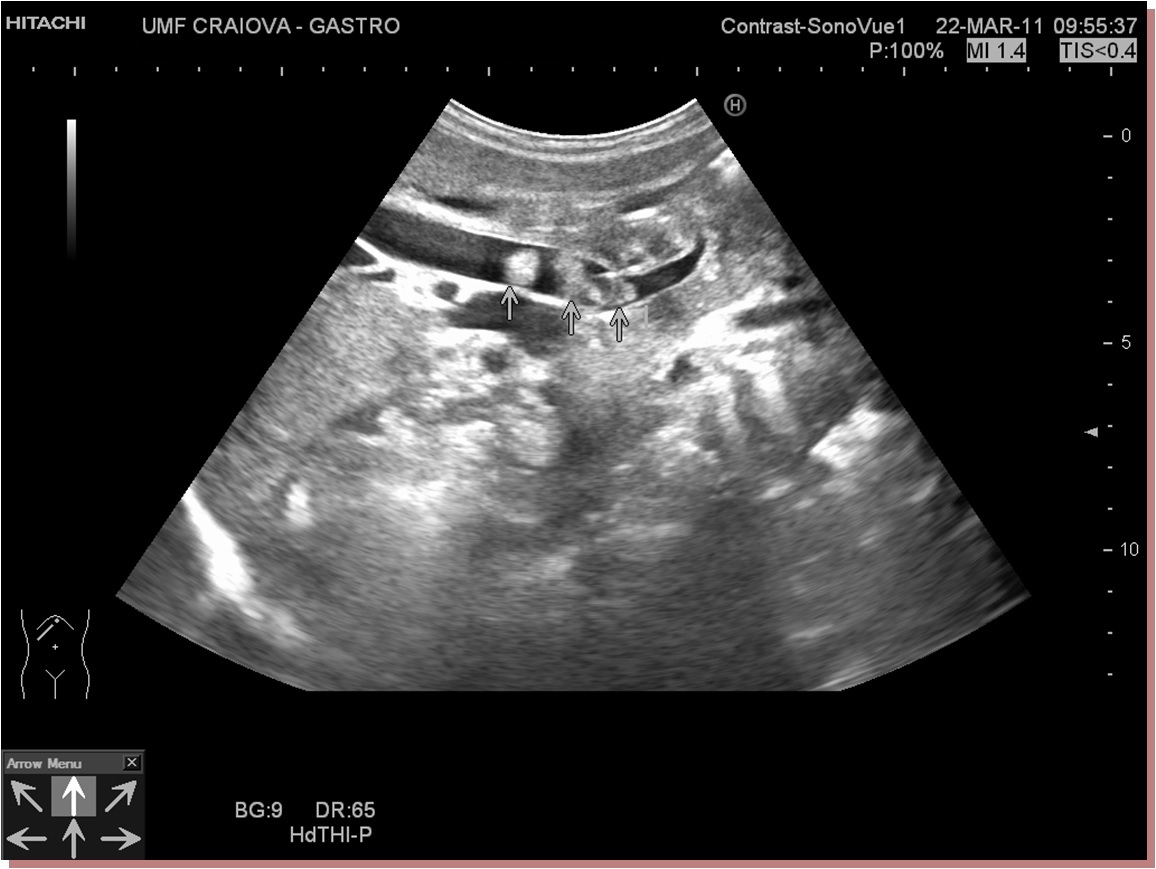

Standard ultrasound shows multiple echogenic rounded images, without shadowing (~20% of common bile duct stones will not shadow) and a dilated common bile duct.